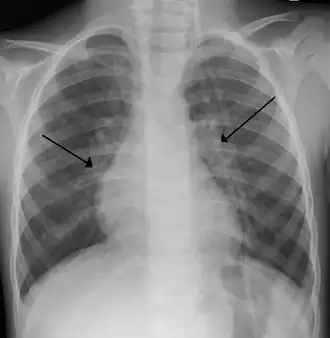

Raio-x de criança com vírus sincicial respiratório

O diagnóstico é tipicamente feito por exame clínico. A radiografia de tórax é às vezes útil para excluir pneumonia bacteriana, mas não indicada em casos com sinais de complicações ou fatores de riscos como prematuridade. PCR para identificar o vírus também não é feito de rotina.[10]